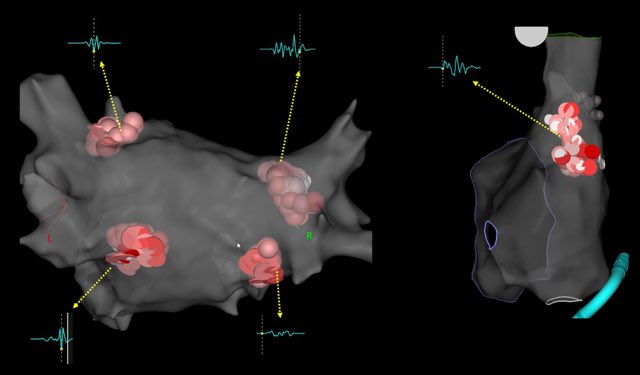

Cardioneuroablation. 30 yo male, coming with weeks of fatigue, dizziness, syncope. ECG sinus Brady 40 bpm. No reversible causes. Atropine test 40>>95 bpm. Final HR 98 bpm, no atropine response.@hhuang123 @FellowEP @DrRoderickTung @gauravaupadhyay

Parahisian PVC, always a challenge to ablate arrhythmias in this region. “We aware of your neighbors @DrFerminGarcia used to say”. Ablated from RCC. @andresenriqueza @FellowEP @DrRoderickTung @hhuang123

Great PVC case today. One burn and gone. Male, 30% PVC burden, EF 42%. Thanks to @ignespinozac for the map. @DrRoderickTung @hhuang123 @andresenriqueza @FellowEP